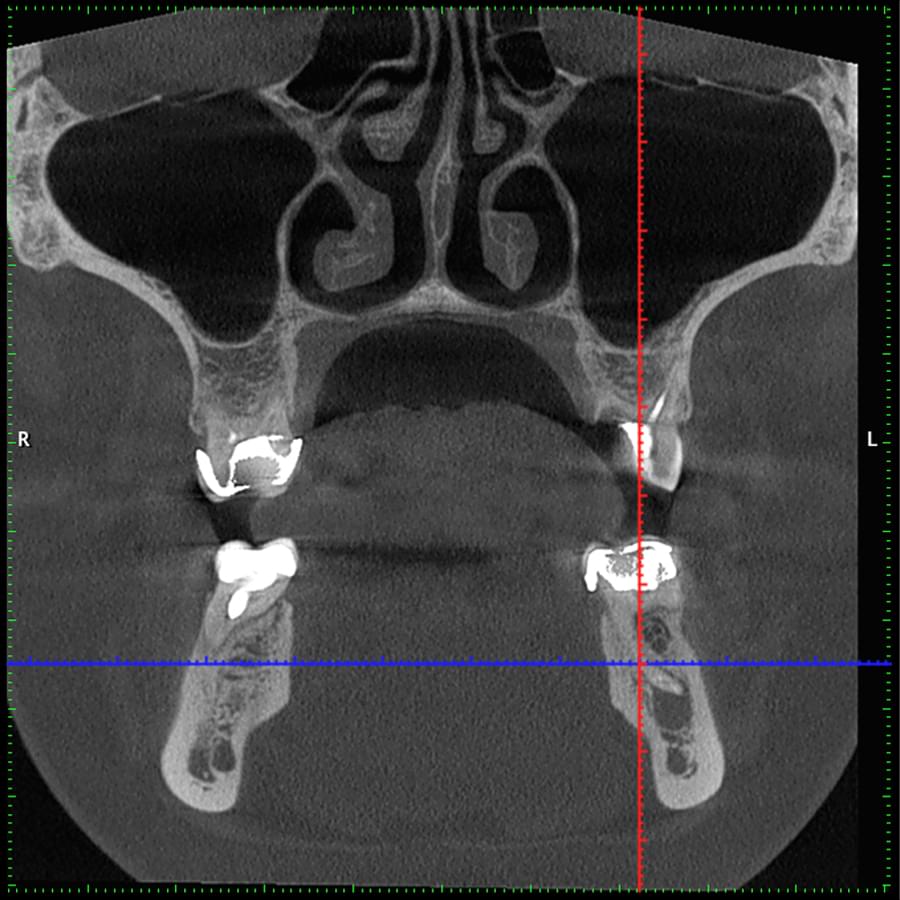

Ми розуміємо, наскільки важлива деталізація в ендодонтії та терапевтичному лікуванні.

Завдяки флагманському обладнанню PLANMECA, ми отримуємо знімки з мінімальним рівнем шумів та

високою роздільною здатністю, що дозволяє чітко візуалізувати морфологію кореневих каналів,

приховані каріозні порожнини та стан періапікальних тканин.

Крім того, ми маємо власний сервер, на

якому створюємо окрему скриньку для кожного лікаря, що забезпечує максимальну зручність та

ефективність роботи.